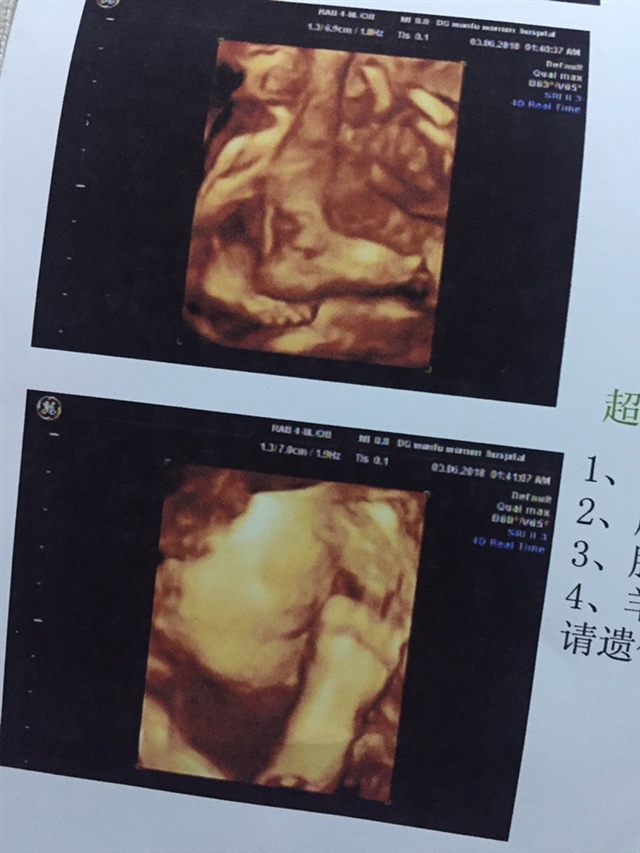

A陳家👑大小姐[帖主]:我22周才约上的,25 5天的时候去查的

A陳家👑大小姐[帖主]:是的,我在深圳预约不到,老公的姐姐在万福有熟人帮我预约上的